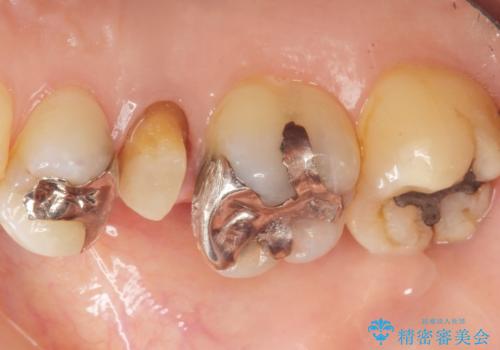

- 歯が欠けてしまったことを主訴に来院された患者様です。

欠けている奥歯(左上5)は失活歯で、保険内の銀の詰め物(メタルアンレー)で治療されていました。

金属の詰め物と土台を除去し、ファイバーコア(金属を使わない強くてしなやかな土台)を植立したのちセラミッククラウンによる補綴治療を行いました。

精査したところ、右上の奥歯(右上5)に根尖病変を認めたため、こちらは根管治療後にセラミッククラウンによる補綴を行いました。